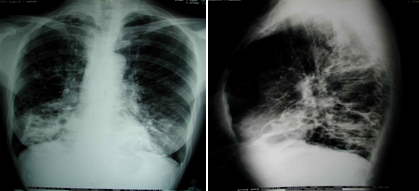

①胸部X線片

粗亂

支氣管柱狀擴(kuò)張典型的表現(xiàn)是軌道征,為增厚的支氣管壁影。

囊狀擴(kuò)張?zhí)卣餍愿淖優(yōu)榫戆l(fā)樣陰影,表現(xiàn)為粗亂肺紋理中有多個(gè)不規(guī)則的蜂窩狀透亮陰影。

女,43歲。反復(fù)咳嗽咳膿痰10年,加重5天入院。吸煙史15年,已戒10年。查體:右下肺可聞及較多濕羅音及少量哮鳴音,可見杵狀指。胸部X線片示右下肺紋理增粗、紊亂。應(yīng)首先考慮的診斷

『答案解析』患者有反復(fù)的咳嗽、聽診下肺部有啰音、有杵狀指等臨床表現(xiàn),結(jié)合胸片:肺紋理增粗,考慮符合支氣管擴(kuò)張。